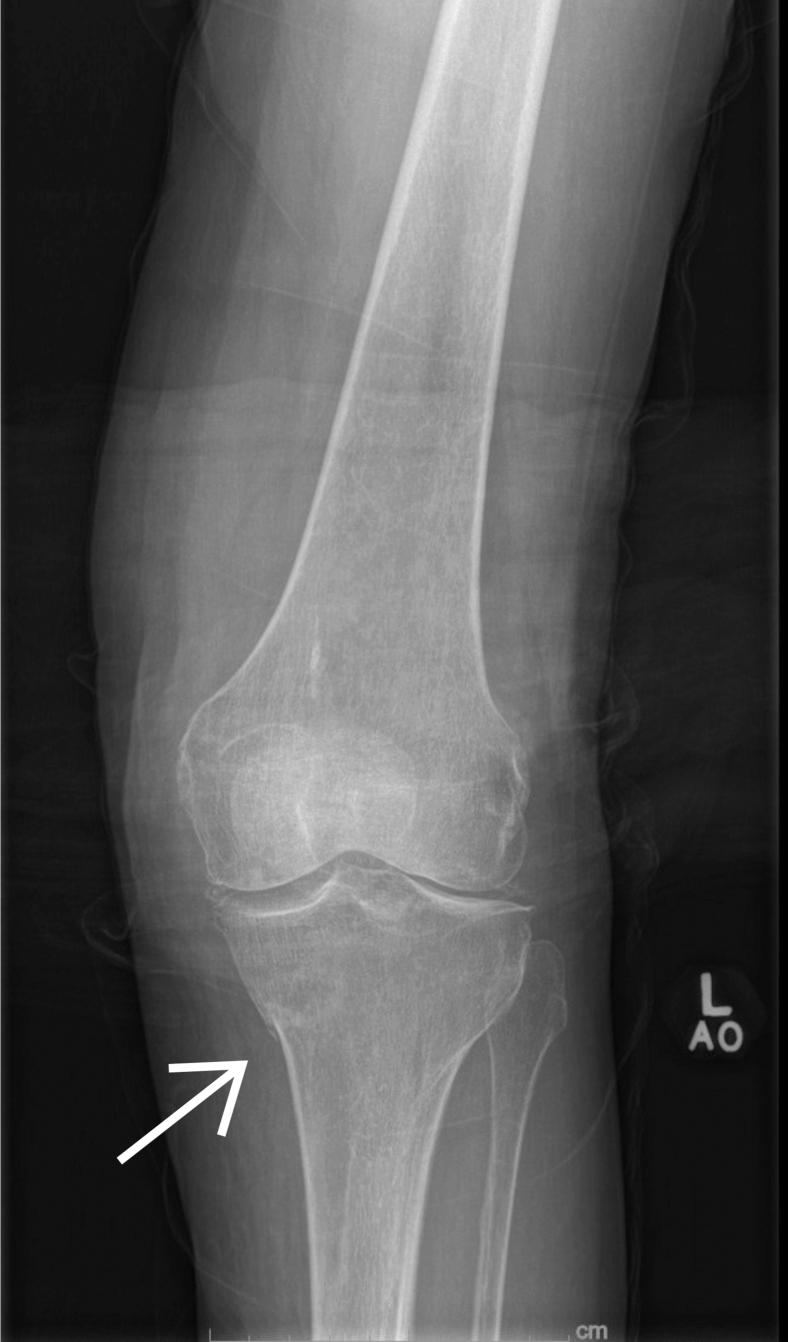

Woman With Left Knee Pain.